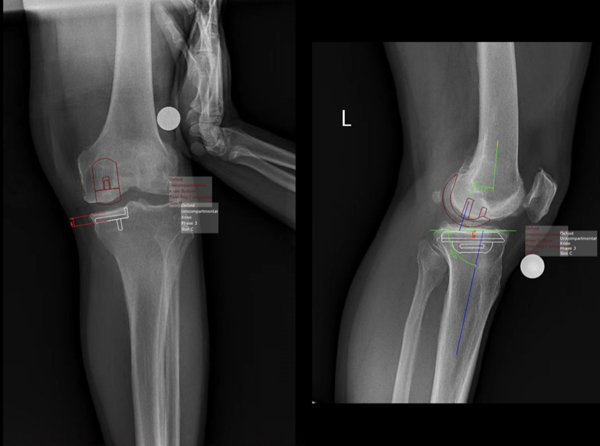

引进德国mediCAD专业骨科术前规划软件,该软件内含全球范围内100多家内植物厂家的电子信息,可以做包括:脊柱,创伤,关节以及运医等几乎涵盖大多数骨科手术的术前规划信息,允许手术医生在二维甚至三维影像的基础之上,做术前规划,做到术前就对植入假体的位置,大小,型号以及不同厂家与不同假体选择做周密,详尽的规划,使手术医生做到心中有数,精准施治。

王伟教授使用mediCAD术前规划软件向中心医院骨科团队展示了系统、全面的术前规划操作及要点。mediCAD可根据患者的个体病变差异,测量、收集关键数据,评估关节病变情况,提高假体选择的准确性,减少了手术后阶段的修正。例如在进行膝关节单髁置换术术前规划时,mediCAD使用"膝关节"模块在两个平面(AP和ML)上规划,计算出预期的术后机械轴、纵轴和所有相关的角度,潜在的轴向错位可以在规划过程中被确定和纠正,使得术前和术后可以评估对整个腿部力量传递的修正,这反过来又大大延长了假体膝关节的使用寿命。目前,在王伟教授的指导下,中心医院骨科团队正全面熟悉mediCAD软件的应用,根据这些术前标准规划文件,病例讨论、术前规划的有效性、技术性都得到了提高,手术疗效得到了更好的提升。